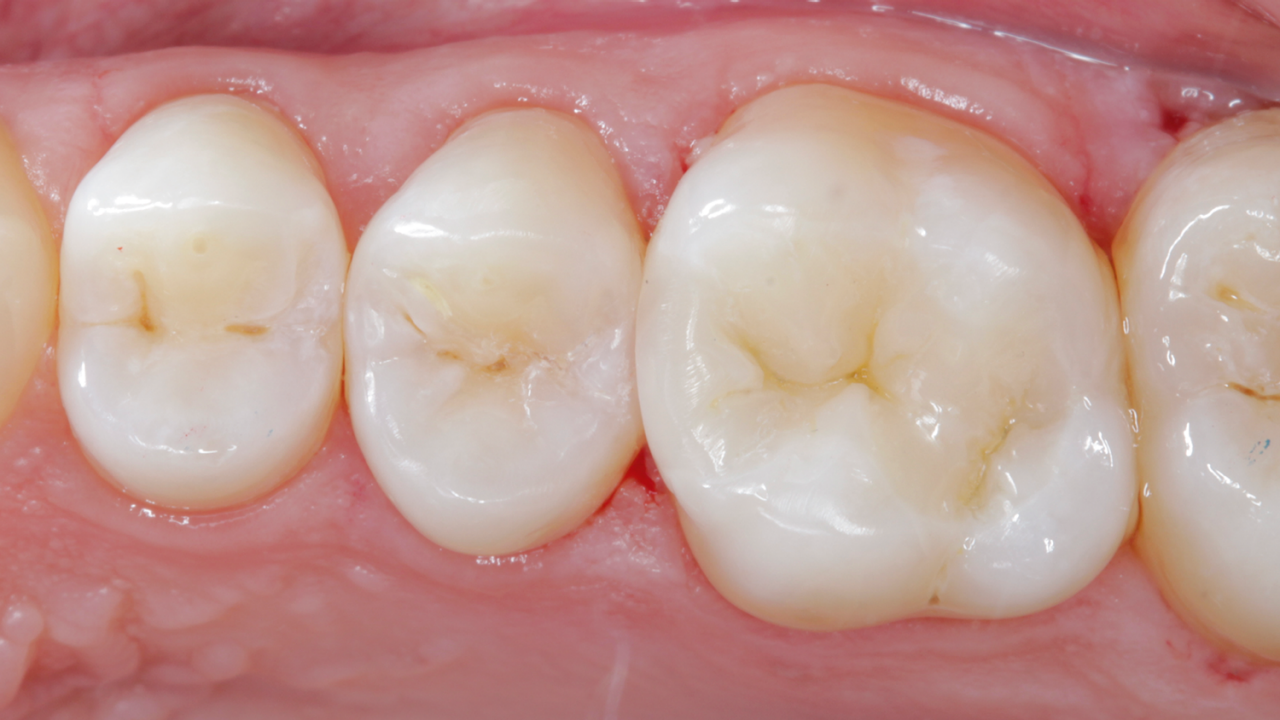

Excellence in class II layering composite

Case: Initial case showing defective and fractured old amalgam restoration.

Results: 3-month recall. Occlusal-palatal view depicting excellent gloss retention. Note the characterization and natural appearance obtained with Ceram.x Spectra ST universal composite A2 and BW.